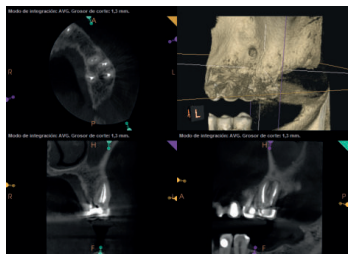

A los seis meses el paciente acudió a revisión sin ninguna sintomatología, tanto a nivel anterior como posterior. En las radiografías periapicales se apreció una disminución en el tamaño de las lesiones periapicales radiolúcidas preexistentes (Figuras 10 y 11). Dado que faltaba tratar la lesión del 25, se realizó CBCT de control donde se comprobó la mejoría a nivel del 26 (Figura 12), por lo que se programó la microcirugía del 25.

Una vez realizada la microcirugía del 25, el paciente no volvió a presentar ninguna sintomatología y las tomografías de control a 12 meses (en 25) y a 18 meses en los dientes restantes mostraron la regeneración de las lesiones periapicales radiolúcidas preexistentes en todos los dientes tratados (Figuras 13 a 16).

Se realizaron controles radiológicos a los 6, 12 y 18 meses mediante CBCT, apreciándose ausencia de sintomatología y reversión del cuadro infeccioso crónico, así como progresividad y estabilidad en la regeneración ósea apical. A nivel del 21 se aprecia radioopacidad periapical, sin pérdida de volumen, y ausencia de invasión del espacio preservado por el tejido blando circundante. Si bien algunos autores han utilizado plasma rico en factores de crecimiento (PRGF) asociado a Bio-Oss® y Bio-Gide® en casos similares al nuestro, hemos obtenido un resultado adecuado sin aplicar PRGF como técnica complementaria13.